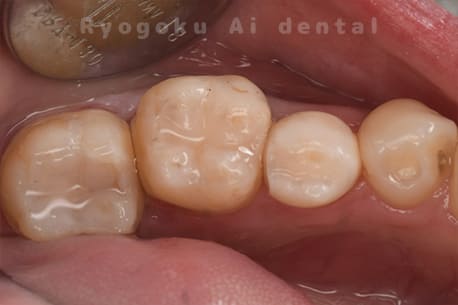

Case27

-

重度カリエス

歯牙移植術直後咬合面

歯牙移植術後咬合面

歯牙移植術前側面

歯牙移植術中側面

歯牙移植術後側面

- 原因

- 重度カリエス

- 治療内容

- 自家歯牙移植、部分矯正

- 治療費用

- 220,000円(移植費用)

110,000円(部分矯正費用)

虫歯が大きく、保存不可能となった歯を上の親知らずと交換する自家歯牙移植を行いました。移植歯が小ぶりであったため、部分矯正を行い問題なく噛み合い、経過良好です。